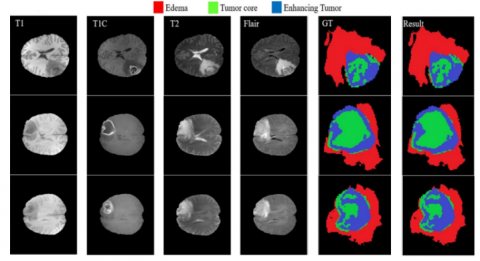

In Figure 6, three brain tumor cases are visualized where each of the tumor cases consists of T1W, T1C, T2W, FLAIR and ground truth images which are annotated by the domain expert manually. The final images in Figure 6 are the segmented results of three cases; the red region in the lesion indicates the edema region, the green region represents the tumor core area, and the blue region is the enhanced tumor segmentation results. Every region has a common border with every other region, as illustrated. The border between tumor core & enhancing area inside the T1C pictures (3rd column) may be easily differentiated with high accuracy rate with no use of other modalities because of the difference in value of enhancing areas & tumor core. When dealing with the border of a tumor core, edoema areas, or exacerbated edoema areas, however, this is not the case. Because of the aforementioned properties of each modality, we see that reducing the searching area eliminates the requirement for a highly deep CNN model.

Figure 6. Proposed model Tumor and edema segmentation results with enhance and core region